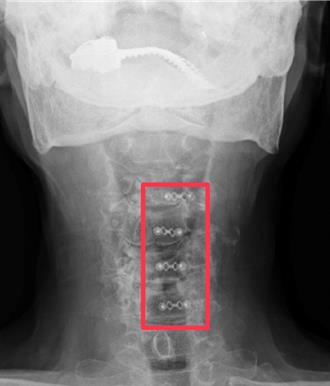

苗栗86歲王姓老翁,雖然高齡卻活力十足,平日還可以到處趴趴走,羨煞不少人,但他一直深受四肢麻木狀況困擾,尤其是晚上睡覺時,時常因麻痺感醒來而再難以入睡,嚴重影響睡眠品質,雙手常常要抖一抖才會舒服一點,直到檢查發現他頸椎管腔多節段嚴重狹窄還合併脊髓受傷,並經頸椎椎板成型手術治療後,王翁大幅改善問題,開心直說終於可以好好睡個覺。